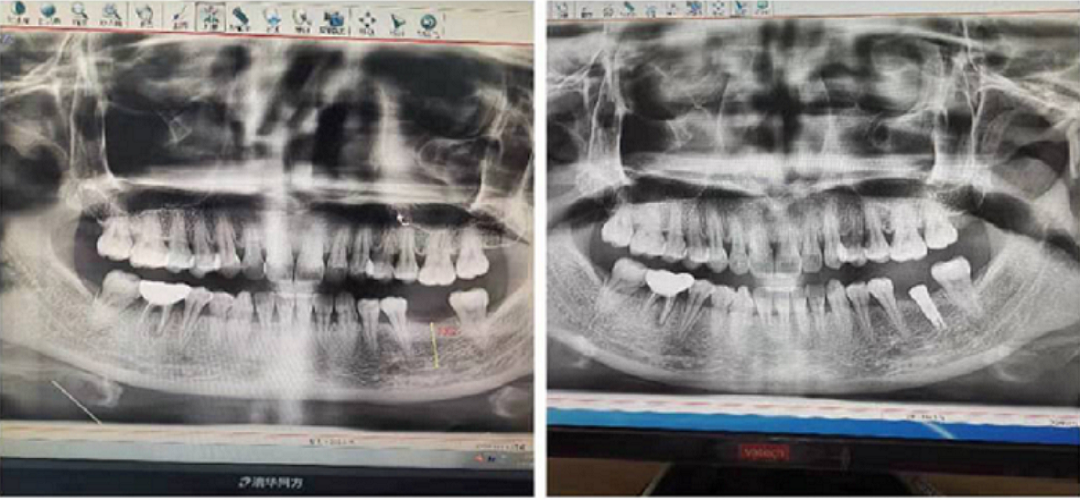

五、真人手術觀摩

實操體驗結束后,張杰博士對一位左下缺失兩年6牙位的美女,種了一顆金泰克的直徑4mm長度10mm 的微創(chuàng)植體。手術過程體中詳細給學員介紹了操作方法,患者整個過程中體驗了無翻瓣的流血的創(chuàng)傷和術后疼痛少,可以正常進食。